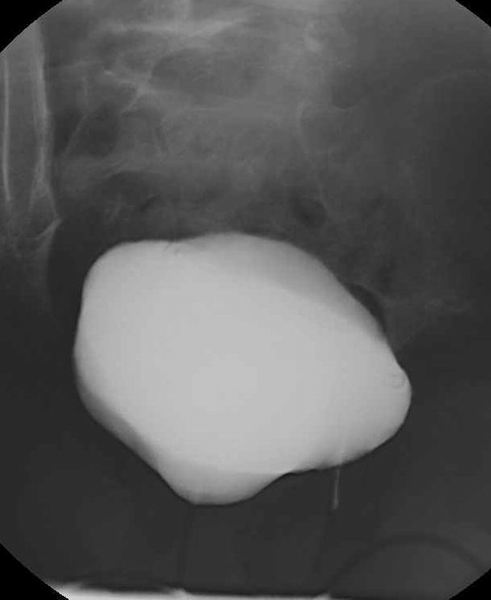

Hystero-salpingografie